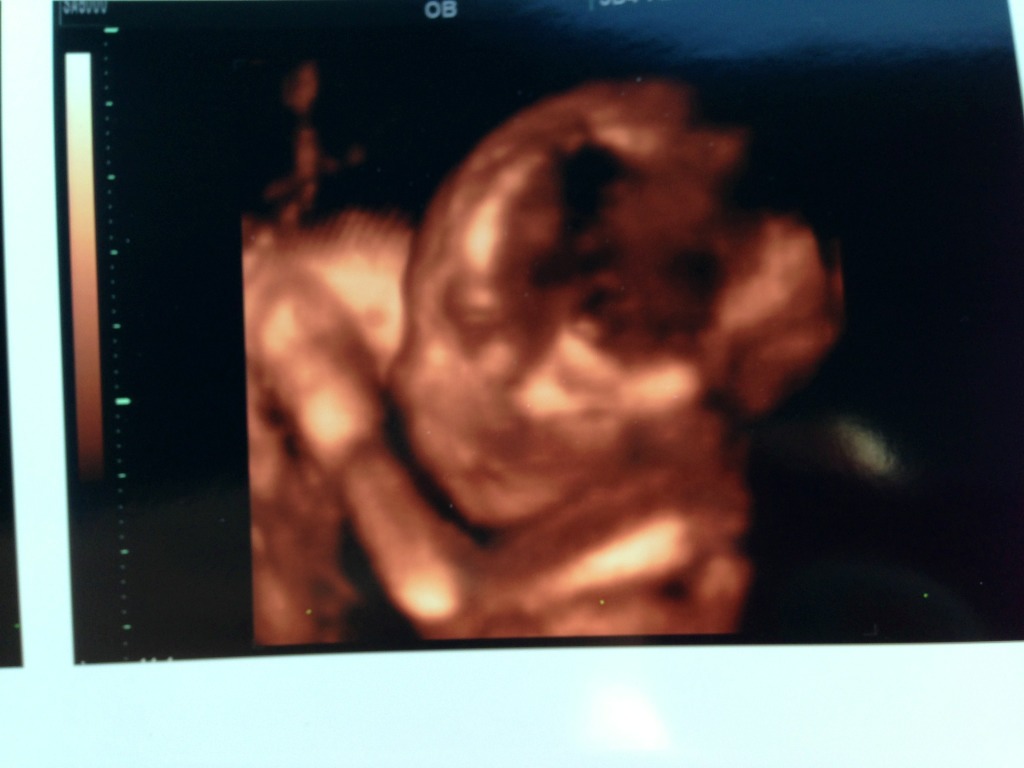

I had an ultrasound today and couldn't see her side profile in 2d only her facing us..